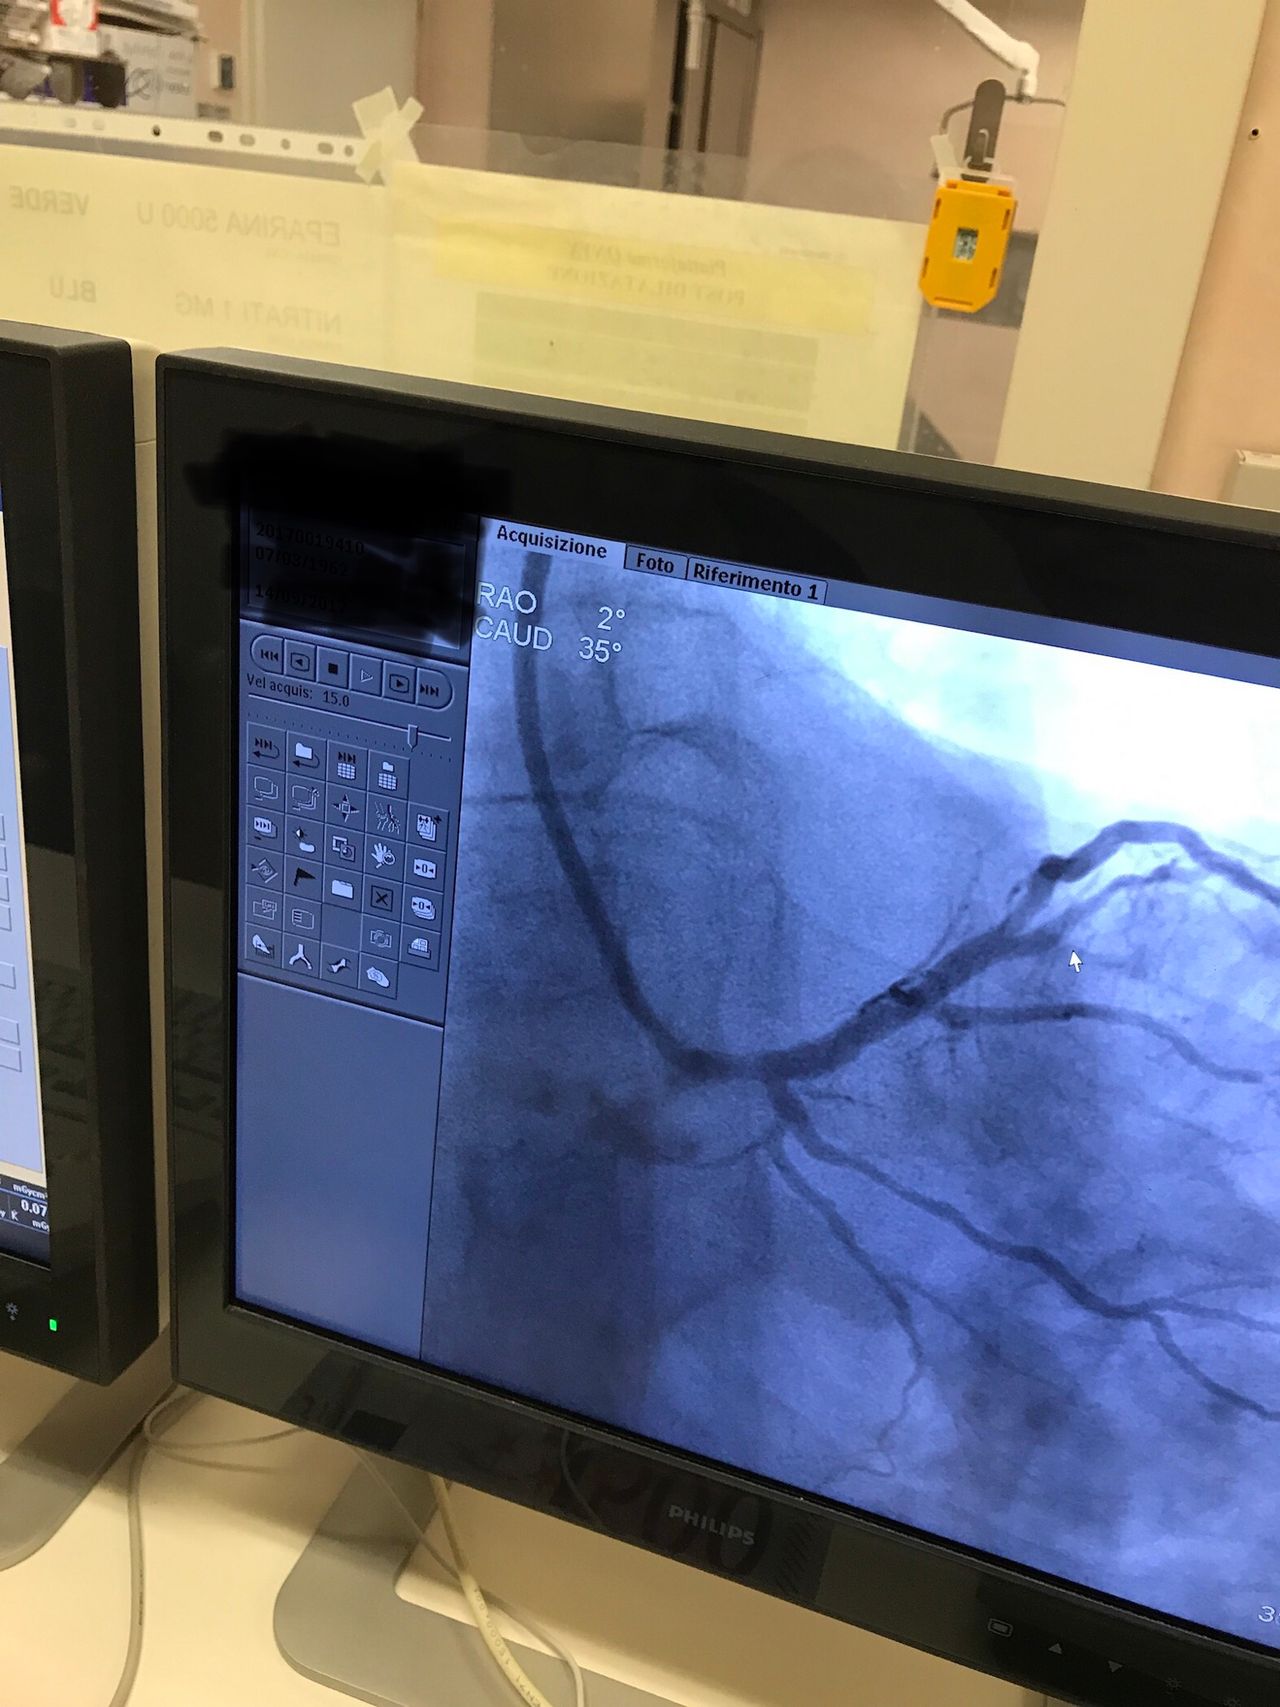

Effettua procedure di ablazione transcatetere e studi elettrofisiologici endocavitari per la diagnosi e il trattamento delle aritmie cardiache, esegue inoltre impianti di pacemaker, defibrillatori e dispositivi di resincronizzazione cardiaca per il trattamento dello scompenso cardiaco.